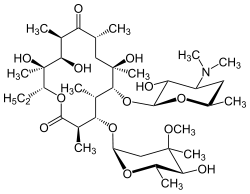

If left untreated, DPB progresses to bronchiectasis, an irreversible lung condition that involves enlargement of the bronchioles, and pooling of mucus in the bronchiolar passages. Daily treatment of DPB with macrolide antibiotics such as erythromycin eases symptoms and increases survival time, but the disease currently has no known cure. The eventual result of DPB can be respiratory failure and heart problems.

Treatment

Macrolide antibiotics, such as erythromycin, are an effective treatment for DPB when taken regularly over an extended period of time.[16][17][18] Clarithromycin or roxithromycin are also commonly used.[19] The successful results of macrolides in DPB and similar lung diseases stems from managing certain symptoms through immunomodulation (adjusting the immune response),[17] which can be achieved by taking the antibiotics in low doses. Treatment consists of daily oral administration of erythromycin[7] for two to three years, an extended period that has been shown to dramatically improve the effects of DPB. This is apparent when an individual undergoing treatment for DPB, among a number of disease-related remission criteria, has a normal neutrophil count detected in BAL fluid, and blood gas (an arterial blood test that measures the amount of oxygen and carbon dioxide in the blood) readings show that free oxygen in the blood is within the normal range.[16][17][20] Allowing a temporary break from erythromycin therapy in these instances has been suggested, to reduce the formation of macrolide-resistant P. aeruginosa.[16] However, DPB symptoms usually return, and treatment would need to be resumed. Although highly effective, erythromycin may not prove successful in all individuals with the disease, particularly if macrolide-resistant P. aeruginosa is present or previously untreated DPB has progressed to the point where respiratory failure is occurring.[17][20]

With erythromycin therapy in DPB, great reduction in bronchiolar inflammation and damage is achieved through suppression of not only neutrophil proliferation, but also lymphocyte activity and obstructive mucus and water secretions in airways.[16] The antibiotic effects of macrolides are not involved in their beneficial effects toward reducing inflammation in DPB.[20] This is evident because the treatment dosage is much too low to fight infection, and in DPB cases with the occurrence of macrolide-resistant P. aeruginosa, erythromycin therapy still reduces inflammation.[16]

A number of factors are involved in suppression of inflammation by erythromycin and other macrolides. They are especially effective at inhibiting the proliferation of neutrophils, by diminishing the ability of interleukin 8 and leukotriene B4 to attract them.[21] Macrolides also reduce the efficiency of adhesion molecules that allow neutrophils to stick to bronchiolar tissue linings. Mucus production in the airways is a major culprit in the morbidity and mortality of DPB and other respiratory diseases. The significant reduction of inflammation in DPB attributed to erythromycin therapy also helps to inhibit the production of excess mucus.[21]